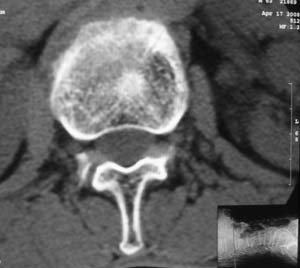

以下是引用余辉在2008-4-27 17:12:00的发言:[br]骨质疏松伴病理性压缩性骨折,椎骨骨松质密度减低,椎体骨小梁稀疏且普遍呈火柴头样改变,椎体无膨胀,无软组织肿块

以下是引用mzh123在2008-4-27 19:33:00的发言:[br]除压缩骨折表现外 还有许莫氏结节改变

以下是引用随光逐影在2008-4-27 21:29:00的发言:[br]除压缩性骨折外,还有许莫氏结节及骨质疏松表现。